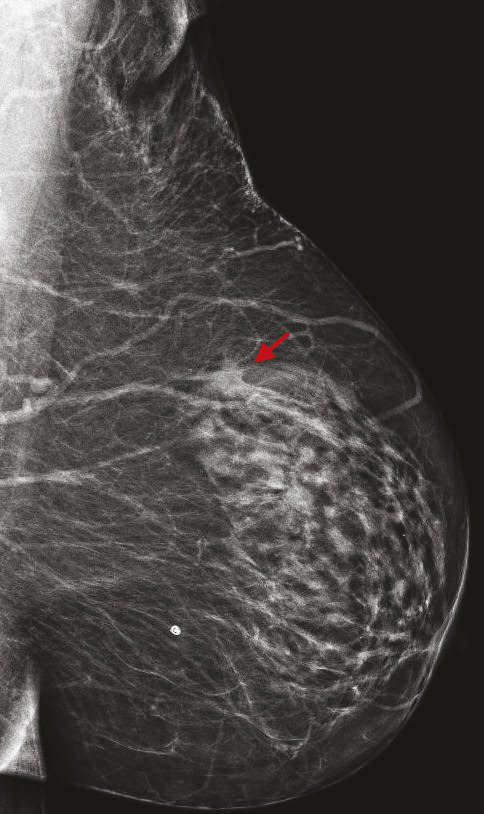

La tomosynthèse est une technique de mammographie développée depuis plus de 15 ans qui consiste non plus à acquérir deux images fixes du sein, mais un volume d’images, par un déplacement du tube de rayons X sur une angulation définie. Ainsi, le nombre d’images varie selon l’épaisseur du sein. L’avantage de cette technique est de s’affranchir d’une partie des effets masquants du tissu mammaire sur d’éventuelles lésions, et de mieux définir les contours des lésions bénignes et des cancers.

Cette technique permet d’augmenter le taux de détection des cancers, principalement invasifs, en particulier dans les seins denses de type C. Une récente étude prospective italienne a montré que la tomosynthèse mammaire deux incidences (face, oblique), associée à la vue synthétique (image 2D reconstruite à partir du volume 3D), permettait d’augmenter significativement le taux de cancers.8 Dans cette étude, 16 666 femmes asymptomatiques âgées de 50 à 69 ans ont été dépistées dans le programme de dépistage de Vérone avec une tomosynthèse deux incidences, comportant une analyse complémentaire de la vue synthétique. Les résultats ont été comparés à ceux de la précédente cohorte de dépistage de 2014, où les mammographies avaient été acquises uniquement en 2D (14 443 femmes).9 Le programme avec tomosynthèse et vue synthétique a permis une augmentation de détection de cancers invasifs significatifs par rapport au programme de dépistage 2D, avec un taux de détection de 9,30 versus 5,41 cancers pour 1 000 femmes. Ce qui est intéressant est que les cancers dépistés étaient plus souvent des cancers invasifs de stade 1 (72,3 % avec la tomosynthèse vs 50 % avec la mammographie 2D), avec moins de cancers in situ (9 % avec la tomosynthèse vs 26,9 % avec la mammographie 2D). Le taux de rappel était similaire entre les deux techniques (4 % pour la tomosynthèse vs 4,2 % pour la mammographie 2D). Ces résultats sont en accord avec les principales études prospectives et rétrospectives comparant l’apport de la tomosynthèse par rapport à la mammographie 2D.10 11